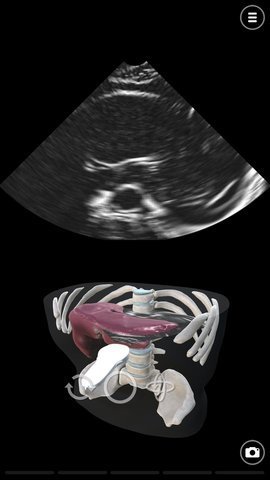

3、超声模拟器游戏的特色在于,它提供了主动脉造影技术,用于对主动脉进行超声波或超音波检查,让玩家可以更加深入地了解超声波的应用。

1、对于心脏病学,游戏还有超声心动图和回声模拟,可以帮助玩家更好地了解心脏疾病的诊断和治疗。